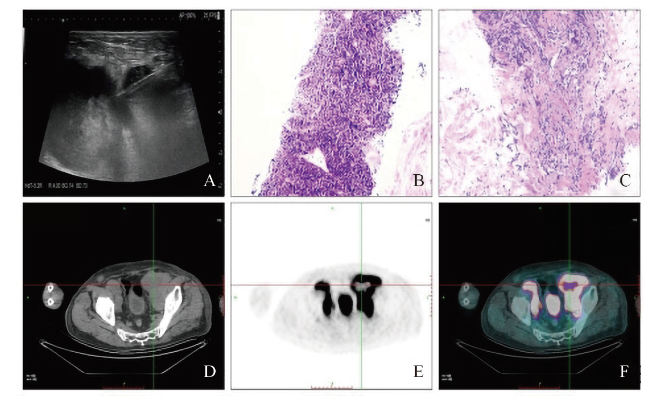

超声造影:于患者左侧肘正中静脉团注造影剂声诺维(SonoVue) 2.4 mL×1次,然后用5 mL生理盐水冲管。观察左侧腹股沟肿大程度最大的淋巴结,可见该淋巴结造影强度呈高增强,造影后12 s左侧腹股沟淋巴结造影呈弥漫性增强,20 s增强达峰值,30 s造影剂消退,淋巴结内部造影呈不均匀增强,部分区域(面积较大)造影始终未增强(图1A、B)。通过超声诊断仪绘制时间-信号强度曲线(TIC)(图1C)。30 min后于患者左侧肘正中静脉追加造影剂SonoVue 1.2 mL×1次,然后用5 mL生理盐水冲管,观察右侧腹股沟肿大程度最大的淋巴结,可见该淋巴结造影强度呈高增强,造影后10 s右侧腹股沟淋巴结造影开始呈离心性均匀增强,19 s增强达峰值,增强过程呈“雪花样”改变,30 s造影剂消退,呈快进快退(图1D)。造影结果提示淋巴瘤伴坏死可能,不排除转移性肿瘤可能,遂于超声引导下对造影高增强区域实行穿刺(图2A)。

图1 一例浅表淋巴瘤伴坏死患者的超声造影

注:A~C可见左侧腹股沟最大淋巴结有筛网样回声,造影见大片未增强区域,TIC示坏死部位无增强;D可见右侧腹股沟淋巴结造影呈典型“雪花样”改变。